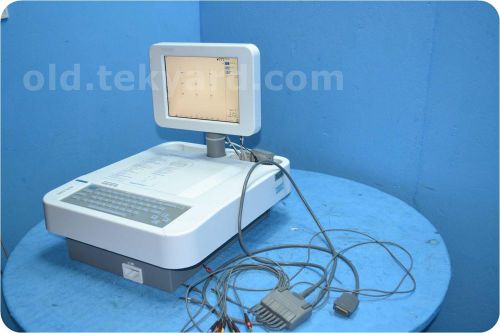

Burdick Elite II EKG ECG Medical Electrocardiograph

QUINTON ECLIPSE PREMIER E10 12 LEAD INTERPRETIVE ECG ELECTROCARDIOGRAPH, EKG @